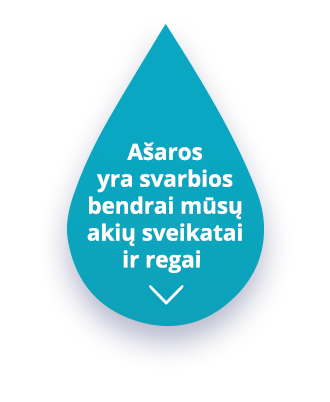

Ašaros yra svarbios bendrai mūsų akių sveikatai ir regai.

Kiekvieną kartą mirksint, apsauginis ašarų sluoksnis uždengia akies paviršių tarsi plėvele.

Jei nemirksime pakankamai dažnai, akies paviršiuje gali atsirasti sausų vietų, kurios kenkia regėjimui.

Ašarų plėvelė sudaryta iš trijų sluoksnių, kuriems veikiant kartu, akies paviršius sutepamas ir apsaugomas nuo aplinkos kietųjų dalelių.

Ašarų plėvelė skirta keturiems svarbiems tikslams:

Apsaugo ir sutepa akis

Mažina akių infekcijų riziką

Pašalina aplinkos kietąsias daleles

Akių paviršius yra lygus ir skaidrus